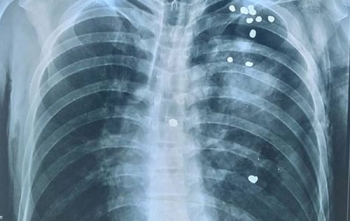

Hy hữu, 20 viên đạn găm vào người vẫn thoát chết

Bệnh viện đa khoa tỉnh Tuyên Quang cho biết, bệnh viện vừa phẫu thuật thành công lấy gần 20 viên đạn khỏi cơ thể bệnh nhân Q.V.D. 46 tuổi.